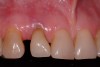

A 54-year-old, non-smoking woman presented with a root fracture at the maxillary right lateral incisor (Figure 1). The patient presented with a 10-mm pocket at the mid-facial probing depth, and a Grade 2 mobility. The preoperative peri-apical digital radiograph can be seen in Figure 2. A natural diastema existed on the distal aspect of the right maxillary incisor, and the patient did not wish to have this corrected. To hold the natural tissue emergence profiles throughout the treatment phase, the immediate implant placement and provisionalization procedure was chosen to treat the affected site. Before the procedure, an occlusal index and registration was taken so that when the retrofitting of the natural tooth shell was accomplished, the exact location of the natural tooth shell could be seated on the implant abutment at the time of implant placement (Figure 3). After administration of an appropriate local anesthetic, tooth No. 7 was removed by an atraumatic technique to preserve the natural soft tissue emergence profiles present pre-surgically (Figure 4). After tooth removal, debridement of the extraction socket was accomplished by curettage of the socket, followed by rotary instrumentation with a course #8 round diamond to ensure removal of all remnants of the periodontal ligament, granulation tissue, and localized debris. To aid in the debridement, the patient was started on a preoperative administration of Augmentin 875 mg, taken the day before treatment, and once again 1 hour before the surgical visit. The patient then continued this antibiotic course for a total of 10 days.

Figure 3  Indexing the exact position of the natural tooth shell.

Figure 3